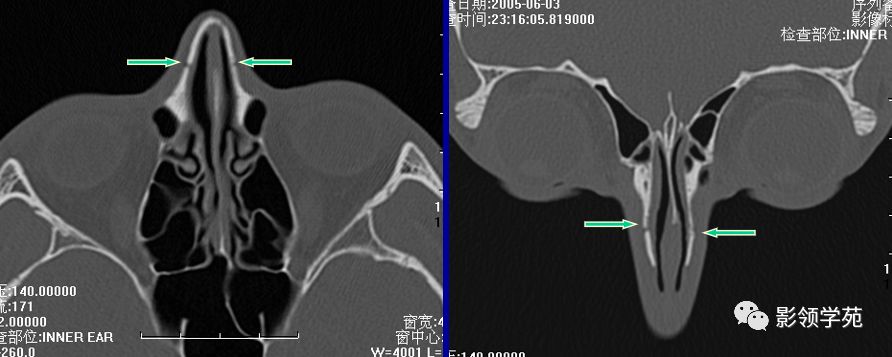

鼻骨横断面HRCT

线性骨折 粉碎骨折

双侧鼻骨骨折

鼻骨间缝